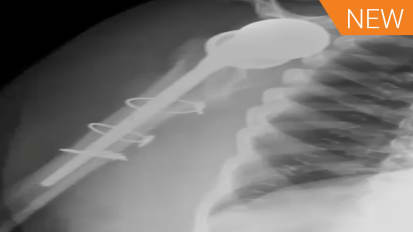

We're very pleased to have Dr James Gregory with us tonight. Dr. Gregory attended Medical School of the University of Pennsylvania and his orthopedic residency at Rush University Medical Center. Dr. Gregory completed his shoulder fellowship at Washington University School of Medicine and is currently an assistant professor in the Department of Orthopedic surgery of McGovern Medical School at the University of Texas Health Science Center at Houston. Also with us tonight is our esteemed faculty panel, Dr George Athol, Dr J. Keener and Dr Robert Tashjian. Dr Atthe Walls, a professor of surgery at the University of Western Ontario, handed Upper Limb Center and ST Joseph's Healthcare. Dr. Athol is also a clinician scientist at Lost in Health Research Institute program of Advanced Surgical Technologies. Dr. Keener is a professor in chief of orthopedics and fellowship director of the shoulder and elbow service at Washington University Department of Orthopedic Surgery in ST Louis, Missouri. And Dr Tash is professor of orthopedics vice chairman for research at a secular donkey and junior presidential endowed professor at the University of Utah School of Medicine and Salt Lake City, Utah. And finally, we're extremely honored to have a special guest Panelist with us tonight. I'd like to turn it over to Dr Keener for that introduction. Thank you, Tim. This is our fourth and final installment, and we've saved a very tough topic for the last, uh, last session. This is Revision Illinois. We're very pleased to have Dr Javier Darryl Day. Uh, join us today. Thank you very much, Javier. Er, um, for those of you in the shoulder world, Javier needs no introduction. He's, uh, been a practicing Children. Although specialists in Atlanta for several decades. Uh, that doesn't mean he's old. That just means he's experience. And he knows what he's doing. Javier is very well trained, and he completed the Columbia Fellowship back when Dr Near was still a teaching. So hey, we are looking forward to hearing his opinions and him sharing his knowledge from his extensive experience. And we really couldn't have a better, uh, guest speaker or faculty for this last topic. So thank you. Have a year for joining us today. So with that, we're gonna have James kick off with his slides, right? You want circle kind of police, Pierre. Okay. So I appreciate the opportunity to talk with everybody today, and I put together four cases that I hopefully think will cover a variety of different spectrum of revision gonna pathology. And I'm honored to be here with the sustained, distinguished Panelists and hope people take a little easy on me so we'll get going, E So, First case. So this is a 75 year old who came to me after undergoing a reversal. Arthur plasticky with continued pain. Um, he had undergone multiple surgeries, including a license of adhesions, development of colonial stress fracture, and then underwent an O production internal. Hey, was two years out from that when he saw me with significant pain and very poor function. These are his X rays. So we've got a Grecian and AP First thing that strikes me is the Camille Plate that we've got here. We have significant superior inclination of our base plate. Then it looks like we've got some ice hostile Isis around almost down. It looks like you can see there's a little crack in his accumulate, which will better see another. Yeah. No, I mean, I was curious sense to the panel. How often have you guys done license of adhesions after reverse? Pretty rarely. Um, I think I've done it once or twice. Um, for those rare cases of extreme Bassett's this after replacement. Um, usually, it's something that I wouldn't do for several months. Um, dedicated rehab. I think in some of these patients with extreme stiffness, you have to worry a little bit about an indolent infection. I've seen a couple of SEAQ knees present that way, but it's not real common to tell you the truth is not a really satisfying surgery. In my opinion, I have had some some success with it, but I wouldn't say it's a game changer, but you do need to think about infection in the back of your mind. What do you think? Georgia? You have any experience with that? Have experienced with an atomic? But I don't think I've ever done for reverse on. I agree with you. Whenever I always think of a stiff, stiff shoulder that requires a revision operation, I'm concerned about the infection. Yeah, you mean I've done arthroscopic release probably twice in my career on an atomic total shoulder and you believe, three years exactly 32. But anyway, uh, so it's very rare. I mean, it's almost never necessary in with the reverse. I worry about component placement, whether something else going on infection. Always you worry about as well. But I don't think I'd ever tackle a reverse arthroscopic, Lee. So I think what I was going to do, that I'd be doing an open approach on possibly doing some kind of revision of the components at the same time. James, can you go back to the AP views on that view on the left, The true AP view. Obviously, there's some scapular tilt, so there's some deltoid dysfunction there. But you see that indentation in the soft tissue there? Uh, it makes you I mean, I've seen deltoid emulsions that kind of look like that. I'm just wondering his previous surgeries. Did he have, like, an open cuff repair? Or he had that open a chromium plating. Okay, they you know, you're basically reading my slides for me. So they took down his deltoid officer cro me in and then put that big old played on and, you know, didn't really repair it. And so he's got a huge deltoid avulsion, which contributes to his poor active motion. Yeah, tough case. A Z still heard of the Crimean or is he just kind of hurt all over? He heard that the chromium, because he's got a criminal non union, you know, broke through the plate. But he also hurt, so he's upset about his poor function. He's upset about paying over the chromium, but he's also upset about he's got a painful Arthur plastic in general. Just abuse me around the shoulder. Yeah, it's where that fracture is on the plate. I mean, that would indicate that it's it's in a chromium fracture. And it's not a capital spine fracture, you know. So those are the cases in which I just think the R F has such a significant complication rate, very little benefit that probably best treated non operatively. You could make an argument if it's the spine of this cap of an entire deltoid is off that perhaps you should fix it. But this year seems like it's kind of overkill. Interesting thing here is that the plate actually fractured. Typically, what you what I see with is that the bone becomes you lose fixation. And so what this tells us is that although the bone that is typically poor, that she has pretty good purchase into the Crimean to get a fatigue fracture of a plate without the chromium pulling off, which is usually what you see. Just interesting. Yeah, it is interesting. The fact they've gotten a criminal satisfactory. Begin with quality bone. So first thing I did with Dr King, you mentioned I sent him for an aspiration infection work. Negative. By the time he followed up, his screw had eroded through the skin on his Comey a plate. So now we had open hardware over his a chrome ian on DSM. Superficial, perilous around that screw. So first thing I did was I deny, indeed, to displaying screws. There was no deep Carolyn's. I found that deltoid essence that we were noticing on the initial A P X rays. I tried to repair through bone tunnels with non observable suitors treated with I v antibiotics, Um, and then with the plan for a stage provision weeks later, because I don't want to do a big revision in the setting of ah, superficial peril infection. So here's when it came time for the revision. So what I found was a central defect. So he had that super inclination of his base plate. It was basically was well fixed, but I was able to remove it and leave a central cava tree defect on. But I was able Thio base can sell us Allah graph through the defect in the news. Say which basically help correct this version. Um, Then I used a san flex stem approximately tapas. You goaded stem with the 36 million hemisphere and Central trade plus six policy. Um, so that's why did initially three years post op. You can actually see, I think nicely. You could see incorporation of the in proportion of annoyed into his. Uh um, unfortunately, with his deltoid dysfunction, uh, he never really got very good range of motion. He had some pain relief from his preoperative presentation, but his a corneal nonunion and his deltoid dysfunction limited him. You didn't really gain much movement. You just had some painful. So, James, when you what was your thought on? Why did you revise the shoulder? I mean, do you do you think? Did you were you concerned about stem loosening or was the Glenwood Inclination your biggest issue? Because I thought I thought the fact that he was getting osteo license around the human component. I thought that that indicated is getting Polly wear potentially some notching or not notching, but potentially some impingement on the interest. Illinois. Um, right here. And so I thought that that could have been a source of pain on DSO. I knew I couldn't really fixes a corneal nonunion, and I tried to fix it, but I didn't really expect that to be successful. And so I thought, if I could give them anything in terms of generally eventually potentially preventing bony impingement on Major E Yeah, James, did you take cultures? At the time of revision, I took cultures not at the tide. Took cultures that the initial um I Indian aspiration, but I didn't e I did. I did Alfa defense again the second time, but I didn't taken hold. Cultures be interesting. I mean, I think you know, one question is you know, e think that X ray on the left shows I think on the medial aspect of the stem, I'm not sure if that's just kind of, um, you know, shadow. But it looks like it was loosened. And so that's the the stem come out pretty easy when you actually, uh, did the revision or No, it did. I mean, I didn't have to do in Aussie Autumn me, So I was able to just slide. It didn't come out. It wasn't grossly loose, But I was able thio just slide nasty to him around the side of it and then easily take it out on and simply, yeah, because that stem is notoriously like even in the UN cemented state extremely hard to take out S O s. Oh, yeah. I mean, that's kind of what I saw. Is that the license around the media card? And so I didn't think it be difficult to get out. And it was we were able to I've got a very stressful for doing an osteo to me to get out stems. And this one was very easy to get out. Um, So, George, I know you, I guess just to finish the thought was that Do you think that there's a There's a possibility that despite having Alfa defense in and aspirations that were negative, that this could have been a presentation off indolent infection that you treated with a one stage anyways by removing it, but it would it would it potentially might make sense that for the stiffness and poor function, etcetera, that maybe that that was that was the case. And I just It brings up the question of Should we be getting cultures on on what? Which revision should we be getting cultures on? And I guess, George, what would be your indication for a culture at the time of revision? Um, so So if I was thinking of doing a Wednesday division, um, and I wanted to play someone, so I guess let me go back. If it's is a mechanical cause for failure, I tend not to get cultures. If I have a suspicion of infection attending the cultures, if I have the option of retaining implants, then I actually do it arthroscopic biopsies because I want to be absolutely certain that if I could preserve an implant on one side or the other that I could do that safely and have my arthroscopic biopsies to prove that, um, with this case, I mean, if you go back, one slide and you look at the AP film or maybe two slides, three slides I've actually seen cases like this where you were on the one view. It looks like osteo Isis. Then if you look at the image on the right, you don't see it. And sometimes you get this artifact from the X ray. Um And so although I mean clinically felt that it was loose. Sometimes I've been tricked this way where I think that it's loose and then you get a couple X rays. You see, the next section actually looks pretty good. Um, the other comment I would make and I think Jay mentioned this earlier on is that there is a substantial amount of scapular tilt in this patient. And when you see scapular till it, I think our mind trains us to think that Glenn oId is securely inclined. But if you see the line of the Super Smiles Foster, I'm not Sir James. Could you put your mouse a little bit lower right there and follow that line? So that's usually an indication of somewhere around, you know, plus or minus 10 degrees from the inclination. So three inclination on this is it's probably a bit inclined, maybe five or 10 degrees, but certainly not excessive. And I think the scapular tilt is what gives that impression that you have a fairly profound, super early inclined base plate. Yeah, that's a good point. I've I've heard, uh, I've heard John Levy mentioned that when he on his a chromium stress fractures, he sees ah, fair amount of notching because they're they're hiking their shoulder so much there. Constant, relatively abducted on they get some abduction impingement, creating some watching eso Um, I guess there's one other issue here to talk about. It's kind of interesting. I don't know the right answer, but when you see deltoid failure in the setting of reverse, I don't know what what you're all success rate has been with with repair. But the reverse, obviously the arm is lengthened. The repair is going to be under tension. If you're thinking that you're going to revise this, um, to another implant later, let's say you don't think it's infected, but you're doing a deltoid repair. You're concerned about the component position. I wonder if there's a role for actually just doing a is removing everything and putting a little hit me Arthur plastics spacer in repairing the deltoid and then coming when you come back in revising it, um, to another reverse. That's where the components are better position, and you've given your delta a time to heal because it's not under attention from the arm lengthening. So obviously, this is a complicated case, and there's probably multiple pain generators and hard to know exactly, uh, what to do in in these scenarios. But I approach infection very much like George does. Eso If I there's a mechanical reason Thio for failure. I don't routinely culture at the time of revision. If I'm suspicious of infection, I do. And if I think I could retain the implants, I do do a lot of scope biopsies. Thio get tissue because I think that's a better way to rule out infection. Multiple people have shown us that, including Bob eso Javier Or do you? Do you routinely culture all revisions? I do, you know, and I don't You know the aspirations don't work because the organisms air stuck into the biofilm, so I don't really pay much attention. That one thing I do do pay a lot of attention to with the it's frozen section. So although frozen section on all these cases and look a number of polish for high powered field and that kind of guys Mia's well. So if I have a very benign looking prosthesis, you know, I see some mechanical issues and then I get, you know, just very few Polish for high power field. I'll proceed with a revision prosthesis, and then they'll take cultures. And then I'll usually, if I have any suspicion, it all. I usually put that patient on oral antibiotics until the cultures come back and then they come back positive. I'll treat him for six weeks with I v antibiotics, depending on the violence of the organism. If I do the frozen section and it looks like it's grossly party lent or it has, you know, a lot of Polly's per high power field, and then I'll put a spacer in and then come back later, treat him and get the final cultures, and then usually come back about three or four months later and and revised the thio another reverse. I think deltoid repair really is, um is sort of wishful thinking. More than anything else, you know that muscles under tension and and basically, you know, I used to do it. I, even for a while, of putting graft jackets over to see if that would help. It is well, and nothing really seems the work. It's just, you know, the world is fighting against you. But I think what you have to remember is, um, even in patients who can't elevate the arm, the ability to rotate and use the arm below shoulder level. If you relieve their pain and restore some rotation in that patient, they'll be much better often than what they were. So it's definitely worth the effort to revise them, just like you did, James. Yeah, um, two things that we just Sorry. Go ahead, Bob. No, I was just gonna say, just to finish out the deltoid issues, I think the mawr common scenario that we often face our patients that don't have a reverse shoulder implanted yet so that they've had some open surgical procedure cuff failure. Um, and there's some level of deltoid dysfunction that's present. And, um, or they've had the cuff insufficiency and that they have a primary middle deltoid head rupture, which we know can occur. Just this, you know, as a native, you know, entity without necessarily having prior surgery. I guess that probably case we've seen a lot more than maybe the reverse that needs to get revised. That already has a deltoid related issue. And so I guess my question would be, you know, to the panel would be in those cases, they, uh, native shoulder or native in a sense that's had prior surgical repair for the rotator cuff has some level of deltoid dysfunction. Um, do you one stage it so you go in and do your reverse and do either kind of side to side implication or trying to bring it back or grafting or whatever your decision due to stage it? And then, um, similarly, um, say that that the deltoid is so far gone. What is a reasonable amount of deltoid loss for you to still proceed forward with a reverse shoulder replacement? It's just anti ahead alone. It's anti head that moves into the middle head or kind of extending even beyond the middle head of the deltoid. What is kind of a A. It is still a reasonable on muscle that you still consider doing a surgical a reverse for the patient to improve pain relief in function. Georgia, I'll start with with So if they have painless lack of function with Delta auditions I'm a little bit concerned about that. I would probably stage that I would do a reverse, see how they well they did. And if they didn't do well, then I do a flip pick If they had pain. I agree with Javier, like if you could take a patient's pain away and give them good rotation, I would do that. I would not do the foot peck, uh, in association with the reverse. I tend to do it stage so I do the reverse first, and I tell them that they're arranging ocean recovery is going to be unpredictable, but their pain relief will be predictable and in a way to, um, And so that's how I approach that one. Um, I would do it staged afterwards. And the other thing that is interesting. So and Javi is absolutely right that we actually looked at our reverse patients after we had done surgery on them and follow them out. Less than 1% of the time is spent above 90 degrees of active for elevation. 99% of their day is spent below 90 degrees, so if you could give good rotation, good paid for emotion below 90 degrees. I still think they have a high satisfaction. Right, Javier, how would you? How do you approach kind of your your patients with, uh, you know, failed open cuff. There's some level of deltoid dysfunction. It's usually some rent that's there with, uh, you know, divot. That's there. And then, um, probably the other cases are ones they've had open Prior Delta petal approach for whatever. You know, uh, you know, a proximal humerus fracture, something like that. That then this kind of lost an entire section and head of the deltoid or even in revision setting. How do you approach those two separate eso depends on it. Depends on the status of the rotator cuff. So I just saw patients today. Four month follow up for that exact sin area where he had complete loss of the entire middle heads of the deltoid current large rotator cuff, tear and, uh, you know, obese. Uh, 48 year old woman, you know, So but no arthritis. And so I took her to surgery, did lights of adhesions revision decompression shit for decompression and did a cuff repair. And she came back today at four months. Extremely happy. She can rotate. She could reach her x l a. She could reach your mouth and she could reach up her because she's got a good subs cap and she she got 30 degrees of elevation. But she got 3/5 strength so supine she could raise the arm up happy, you know, told me that about 10 times. So I think if you can fix the cuff, try and do that. I didn't even attempt to do anything to the Delta yourself. Well, she had innovated deltoid as well, so different. Now, if you have that scenario and it's irreparable cuff and you're looking sicker, there's nothing there to work with. I think that you need, you know, if I have ah, isolated loss of the middle head of the deltoid or anti your head of the deltoid, I'll consider doing it because if the entire heads down, they still abduct and kind of bring the arm out sideways and you use it and have some function you know, at at Children level in the same with, uh, if you know the middle head's gone, they could still have some forward elevation. They lose the two of those on a massive rotator cuff that I just don't see you have much to work with. Very few patients would be, you know, candidates for fusion. But I mean, probably the breed Mont do little or nothing on those kind of patients in my hands. And maybe that's the patient George that you were talking about. We're doing the transfer and that if you have kind of gone all the way around the side, then you're talking about Boston's tech transfer toe. Try to help him. We have a We have a question from the listeners before we move on to case number two just, we'll just quickly scan the panel. Any indication to revise the Crow male fracture? Javier, in this patient? No, no, it failed once. He's gonna fail again. Yeah. Uh, no. Only if it was a spine fracture for May J. Yeah, I agree. Just the location of the fracture. I probably would not have fixed it at first. And the spine fractures are there different players? I would. I think it's worth fixing those. I've never revised the failed our f of the spine fracture, but I imagine if there's not too much bone resorts in at the fracture site. You could consider that. But we know that people with a chromium insufficiency prior to reverse do well and even the ones with the post op chromium fracture. As long as it's not involving the base of the spine or the, you know, base of the chrome Ian or medial spine they do. They tend to do pretty well. They lose a little bit of elevation motion, but I don't think that's enough of an argument to fix it, so I would not able advised it, either. Segue. Case number two I thought this one because it was a central contained defect. This is how to address revision clinically deformity. I grafted the central defect and could easily gain central food purchase. So Case number two So this is a 67 year old underwent a right reverse for 2015 presented me three years after the index surgery, had really, really pretty good active Ford elevation, but have significant pain with a deduction. So we heard whenever his arm was down by his side. No pain with a deduction or movement around the arm when he was elevating it. No history of instability. And so here are his X rays, So same thing we've got to AP views way, see superposition of the base plate. We appear to have appropriate inclination, but there's a certain amount of bone in proportion of Illinois way, which makes sense when he's hurting when he's a deducted. Um, it looks like he's in pinching his Glenroy tray or is metaphysical force humorous? I proportion is finally okay. This is excellent. It's a J. How would you approach this one? Um, well, I think James has kind of nailed it. The base plates high, and sometimes that's well tolerated. If if you're a Missouri medium and your 253 £100 and you've got a big a big biscuit underneath your arm, you're not really spending a lot of time abducting. So sometimes, um, that's pretty well tolerated, but, um, I would approach this with a C T scan. I tryto better objectify where the base plate is. You can see just where the central screw is and, uh, the reference of the base plate to the superior, literally that it's high. Now the question is download. Where's the native joint line? Because some of that bone is probably reactive, hetero topic bone. But I get a C T scan of the shoulder. Um, if you're concerned about the hue mural implant, Uh, sometimes on these revisions Uh, not so much in this case, but instability cases. If the implants put in too low or there's a length issue, you get full length humorous films. I don't think I would do that in this case, Um, S O I would probably get a C T scan. And you know, I think it's reasonable to revise this on, Duh. Revising the base plate with the thought of retained retaining the human component if it's well positioned, Sometimes you get in there and you find that the versions way off or or if it's not a platform system, you have to revise this them. Anyways, eso those were those were kind of my initial thoughts. Is this a striker? Uh, a strike? It looks like a striker. Sometimes, uh, it's got 135 degree head neck angle. Yeah, Sometimes you can keep the base plate. And if there's Glynis, fear modularity options where you can either latter lies or or have some east interest. ITI to bring the head center down. You don't have to revise the base plate, but I've seen a few of these that are way off, and there's actually they're actually fairly easy to revise because there's enough real estate of Glenroy Bone in Fear, Lee that you can get primary fixation. So I've seen that a couple of times, but never we ever considered just doing a notch plastic. So just going in there and removing that bone is that an option? I think it's an option if the base plates recently well positioned, especially if you can add a little bit of lateral ization on the Glennis fear or some eccentricity. But and you know, when you get in there, you're gonna find a lot of Polly wear in fairly. You're gonna find a ridge of bone. You can certainly bird that bone down if you carefully exposed the in fear of Illinois in exchange the poly. But you know you have to make some type of a judgment if you think, um, if you think that's gonna be enough and that's hard to do sometimes inter operatively. But I have done that on cases where there's Mawr bone projecting laterally But I think in this case, I would be concerned about that. It probably consider, uh, either modularity options on the head or advising the base plate. Uh, would you do anything different? So I look at the left hand ax right there and that that component is already contract is already pretty lateral eyes. You know, something worried about putting in a Glenn was fear that was bigger or more lateral eyes. But I agree that sometimes you can if you have any centric one that you can rotate downwards and cover, you know, the inferior part of the Glen oId rim. And perhaps between that and removing some bone there, it's possible to do it. But sometimes it's a mess down there, you know, with with Polly wear and the inflammatory response a patient has to it so often, the bones of worse condition than you expected to be from the X ray just because of all the, uh, Polly debris. And then they're the microfiche reaction to it. So I think more often than not, you wanted improvising the whole thing. Um, what did I dio? That's the whole thing. So when I got in there, I found that that stem was 20 degrees and averted. You can kind of get a hint looking at his axillary x ray back here. Eso I felt it was appropriate to revise that stem. I was prepared to retain it and try to just provides the late But I ended up doing the stem was well fixed, so I ended up doing an aust IATA me. I create a little estrogenic frosty fracture that was non displaced. And then I actually found his base plate was loose so that basically it was completely loose. It was very easy to remove. E was actually, as you pointed out, I was able to use the inferior Glenroy, which was relatively well preserved and then used a full wedge based augments, um, to help. Correct appropriate position, inclination. Pretty good purchase of our central screw your base plate position Looks great, James. I think this is a good indication for the augment as well Give yourself you're gonna you know, you're gonna have bone loss. A purely obviously. So you can make that up fairly nicely with these augments. Um the great existent. Sorry, sir. Go ahead, J, I'll go ahead. E I was gonna ask you so J, in this case of with a loose space. But when you consider getting cultures at this time Indra operative, I would I would culture that because I wouldn't expect Anabel rent position base plate to be loose, so I would probably culture it. Um, I would do frozen sections as well, because I have to make a decision at the time of surgery. And I'm gonna advise this or am I Do I think it's infected? Um, but I don't know. The utility of frozen sections is debated. I think there's probably a role in borderline cases, but I would I would culture it. I would wash it out as if it were infected. Changed my gloves, changed my gowns, get a new table in the back and try to put this new implant in a sterile as I can. Um, I don't know. What would you do, George? Would you culture it exactly? I mean, I agree with you. It's pretty rare Thio to find a loose Glenroy basically s Oh, I think I would agree with you. I would do a, um, culture at the same time. I do aggressive irrigation department probably treated like a one stage and put him on I V antibiotics until the cultures come back. Mhm. But this looks great. Bass player looks perfect. It does look good. I had a patient like this. It was a renal dialysis patient. And the bass player was completely displaced. Sure, she was infected. We went into, you know, revising and got in there. And it was Paul Polly wear, you know, And, uh, frozen sections were negative for any type of bacteria, and cultures came back negative. So, I mean, it does happen for different Polly, where I would agree with probably more likely to be infection. You gotta be very suspicious of it. But sometimes that can happen. You know, thes augmented base plates for the revisions in the primaries that tend to use, you know, autographed photograph from the human head. But I think these air really very versatile in these kind of defects. James, with this, So is the Cirque Lodge there securing your tube rosti factor? No, it's a currently osteo bi. Okay. And so you're to grasp the fact it is pretty high, though, right? It looks like it's very high. It's right. It's right here. Yeah, eso. It's just essentially, I went back to the first of the pre op film. Yeah, that one. Just so the only thing I'd say about this is this is the striker base plate. I'm almost positive they tried to replicate the D. J O N Plan. And so I don't think that there's a central post or any in growth central fixation. It's all screw fixation. And so I personally think that that there's probably a to see a loose base plate with This would not make me as concerned with regards to infection simply because I think if you've got any type of mechanical problem with inside the shoulder, you're probably a much higher risk for having this base plate loosen as opposed to something with an in growth post or central kind of fixation. So, um, whatever it's worth it, you know, there's nothing for those screws to grow into. It's just, you know, stainless steel or titanium. And so, um, it's something I would think about that if you're gonna when revising a base plate that is all screw fixation with no uh, in growth post that you might have a higher risk of having a loose base plate without infection. Um, the only other thing is like if you look at your you can see your your left handed image on the left side. And then if you scroll forward to your post op that you're chromium humorous distances probably increased by, you know, double. And I think that's probably or at least 1.5 that you clearly lowering your sphere. But I think it's also, um, the type of humor Elim plant that you've used. And so that s O. The only other consideration is I think this looks great. But if this was, say, a 75 year old female, um, I might get, you know, osteo product. 75 year old female. I might get a little bit worried with bringing her down that far from where she started and maybe consider something Mawr kind of in Les instead of online toe may be uploaded, but those I don't know, those would be my only thoughts. I think it looks great, though, so I was pretty happy. Patient was pretty happy for a six week post op visit, and he was out, told me he went hunting and went was in a deer stand and something was falling off the deer stand. So he reached out his like ammo box or something. Um, so you know, I thought I was putting him into tight, but clearly not. So we ended up revising him. I found that his human stem was actually loose, so I advised him to a daffodil president stem. I think in retrospect, that greater to brasi fracture that I didn't make too much of, I think compromised enough of his fixation of that metaphysical stem that it it didn't really work. That putting them. Uh, no eso I picked this one because this was superior inclination of basically a superior Illinois bone loss category defect. But we didn't really have to address it because we had enough real estate in purely to just basically play it as it lies. Eso we didn't really have toe to do much beyond usedto basically to address this plan. So case three This was a 64 year old male with hemophilia who underwent a total shoulder in 2009 did well initially and then gradually had worsening pain limb to function. Now he's got 10 out of 10 pain. Very poor active motion he's got will preserve passive motion and significant rotating weakness. Here's his initial X rays in 2009 s so we can see what looks like a field components Looks like, you know, people have position, maybe a little bit high dial high. But the Glenroy it appears to be, well, positions or the country component is well positioned. 2019. Can you go back? Yeah, so was he's got an anchor in his greater to Barazi. So he's had a cuff repair. Was that done prior to the time of the replacement? Do you know or at the same e Don't know whether it was done before, but he had, He said after surgery he had excellent function, so I don't think grossly insufficient time. A human head looks like it's touching the a chromium there, you know? Yeah, Glennon components high also, which would also probably promote the human head from going on. You see, the keel is almost at the level of the Super Hispanics fossa and and these were put the initial The surgery was in 2009 right? There's initial post op X rays. You see, the state. The state staples on the right, actually, but you don't see the smooth. You know, this is for user benefit. Once, two weeks later, then no. Yeah. So in general Bob, what? Your thoughts on doing an an atomic replacement in a patient who has had a previous cuff repair. If you think they're cuff is intact and they they don't have proximal migration, Um, do you? Does that concern you at all? It does, And I've I've gotten to the point where it's extremely uncommon for me to do in an atomic shoulder replacement someone that's had prior rotator cuff repair despite having kind of a memory. Even that shows that they've got a healed rotator cuff just because of the overall quality of the rotator cuff. Integrating into the into the you know greater to ferocity. It's interesting that last week I saw patient who she was post from a rotator cuff repair, and she was perfectly well centered memory. It was perfectly well heeled, and her motion was excellent, but mostly it was internal rotation. That was great. And so I told her this exact same thing that, you know, we went through this, that I normally would do a reverse shoulder replacement for her. Specifically, I am going to do in an atomic because I'm afraid that I'm probably gonna lose motion with her if I do a reverse. And she might very well be unhappy. S o. I think there are cases. We're doing a reverse. I can Atomics. Reasonable. But I'll be honest, like nine times out of 10. I'm doing a reverse. How about you, J? I've done it and I'm concerned about it. I don't know what the right answer is. I think that I would I would definitely one image ing that showed not only the cup was intact, but the Muslim bellies were healthy. They would have to have good preoperative range of motion. But I've done it and I've not. I've not been burned that I know of, but it is a concern. I don't know. You know, it's an interesting thing to talk about. Well, I think because I mean, if you know, if you like reading about an atomic Arthur plastic in the setting of a full thickness rotator cuff tear, it would suggest that the outcomes of an an atomic replacement are not influenced by the status of the rotator cuff, meaning the presence or absence of a terror. Even in Paschal's, you know, paper that him and I think it was it was Brad. I think that maybe was butch, that showed that it was the muscle quality of the infra spin. A tous was predictive with regard to the function of the an atomic. It had nothing to do with the presence or absence war, the presence of a repair or not a repair at the time of an an atomic shoulder replacement Joanne Audie and Tom Norris. You know the same thing in their data and but did the same to Yeah, but I'll be honest anecdotally for me every single time I've done an atomic replacement and done a rotator cuff repair. The patient comes back, and either they're painful and weak or I gotta convert him to a reverse. So I hate toe practice anecdotal medicine, but I'm like, I'm not going to go there again. And you know, you do it kind of a couple of times, and you're like, I'm not going back. And Javier, what? What's been your experience with that kind of very similar very similar to yours, you know? So you know, we used to always say the anatomical is indicated in in, uh, intact and reparative cuffs. E think that's true. So if a patient has a tear the time of surgery better off this with the reverse to start with. If I had a patient who had, like, a small cuff repaired years before and the imaging looks good like they've got good muscle bellies and it looks like the end of the, you know, healed Fine. I'll think about doing an atomic in those patients. I also feel like the cuff is gonna let you know during surgery sometimes whether you're making the right choice or not, because you started doing external rotation and the cuff tears off and let you know that was parchment there. And so So I team up for both, and I tell them if if it's I just say if it's poor quality during the time of surgery, we're gonna do a reverse, and so I don't go through the details. But if I'm actually rotating and dislocating and it tears off, they're going for a reverse. It looked like 10 years later, in 2019 um so we can see if you look at the metal or the little regulation markers of the keel on the extra in 2009 you can see that significantly migrated in 2019. So we don't really see those as well on the axillary. What we see them translated more post yearly thing. They were here. They are centered in the glen. OId looks like they've moved most clearly, so it looks like one component is possibly loose and has migrated. Posters superior. Another thing I look at is if you go back to you, look at the position of the greater to Broschi in reference to the lateral aspect of the Caribbean. So go back when slide if you could. And you see there's about a centimeter to breast about a centimeter latell to the corona and you see the next film that's me realized on so many times. In this case, you were really good because you can see the Glenroy failure. We've had cases where the Glenwood actually looks pretty good, but what's happening is it's just slowly migrating, and even though it looks good, we know it must be loose or slowly becoming loose. just by looking at the two bras too. So I got a C T scan on this. Um, this is a cut on the left is the in proportional Glenroy, which you can see the Glenwood Component appears. You know the position, Superior Lee, you can see that, uh, the clinic component appears to be completely uncontained. And so it's worn out of the poster super aspect of Illinois, which is consistent with what we saw. Radiographs. So it looks like a loose, gonna component, significant pusher, Superior Conroy, bone loss, um, and likely rotator cuff failure based office. Sam. So here's what I did. So this guy is, as I mentioned, severe hemophiliac. So it was an ordeal. Getting him optimized for surgery, you know, preoperative invention. You know, factor seven for, you know, several hours and then mission outwards. So when I got in there is his preoperative infection. Work up again was negative. I did take cultures on drop. Really, Given the loosening, I had thermal had telegraphed available to address the bone. Um, if I thought I needed it, but I was actually able to do this in one stage. I use a little bit the alternates Capital Line to get fixation with my central screw, as able to reference the infra portion of Glen oId and use a half wedge base plate, um, to and I'll have to post your support to post your super portion. The based played a little bit uncovered, but I had approximately 80% coverage at the base plate. Eso I felt pretty confident with that. I didn't want a two stage in because I don't want to come back and someone with significant medical capabilities. Um, so you know, I used to have so fitting stem, but I'm pretty happy with the fixation was able to get in with a challenging clinical deformity. Mhm. So I've got a SYRIZA about 10 patients like this, and many of them were frail like this guy, where they show up in their their high risk for surgery. And I've gone and done arthroscopic excision of the Glen oId biopsy culture at the time to see if they're infected and they've done pretty well. What was this guy's function pre out very port. So he had, I think, 60 degrees, 80 degrees of active Ford elevation. Andi Way had actually I you mentioned that Because that was the interval step. I actually wasn't this guy, but I've done that before us. Well, and, uh, you know, it's been mixed results is cuff weakness and poor active for television That though I ended up deciding to go with the reverse, But I think that's great. Interesting. If you go back and look so if you look in a C T scan, he's actually surprisingly, is infra spices. Subs cap have almost almost no fat infiltration. When the image on the left just a surprise. Yeah, yeah, you know, it depends, I think, on what the functions like what the patients like and risk Andi. You could also do that The stage procedure, you take the glen or it out. You do your biopsy to find out whether you have an infection or not. And then you can judge whether the patient is gonna be happy that way or not. And if he is, you can let sleeping dogs lives. We say here in Georgia, or take him back and do the reverse later. Yeah, I think I mean, for me, the arthroscopic Leonard component, Great pain relieving operation, at least personally. And I know that people have had kind of different opinions with regards the effectiveness of it. But I think it's been, um, tremendous. You get a all that debris out. Oftentimes a Glen Oise cracked in half or it's sheared off. And, um, from a functional standpoint, though, I haven't necessarily found very much improvement for patients that they're still weeks still can't raise their arm. But, like you said, if someone starting out with decent function, 90 degrees of elevation and then maybe it's just a big pain issue low demand, I think that I agree it's a great operation. Um uh e I think I've got about 10 or 12 of very similar to Javier. And it was My indication was either the Glen was loose or they have a painful shoulder that you're gonna go in to do the cultures on to take the five biopsies and the Inter operatively ahead about three of them that we identified that the Glenwood was loose and if I looked at all of them, about 50% of them did well, 50% of them will end up getting revised. So, James, can you talk a little bit about the alternate center line and how you find it in the O. R. And like is are there some tricks that you can use to find the that column a bone that you're looking for? Maybe just for the for the for the audience. Yeah, And so the idea is, you're really Instead of the normal kind of perpendicular to the normal Glenroy face, you're going to really try to get your center pin or the access of your center of your base plate through the high quality bone where the established by Mrs Scapular body. And so that's gonna be more an averted than your normal, um, access. And so what I do is I slide my finger around anti early and do it under PAL patient. And so, basically, you know, I can feel where that column of bone is with my finger and I'll shoot my guide wire. You know, freehand essentially and kind of palpate with my guide wire. As I get down and estimate the quality of our the depth of the vault that I have with my guide wire. Compare that to the length of the boss that I have on the back of the base plate. and determine whether I'm gonna have enough to actually get a screw past the boss. And in this patient I did. So I felt comfortable doing a one stage. If I don't, then I would do a two stage. But that's, you know, you're basically trading the version of your base plate pay putting, um, or an averted for getting better bone, which is very helpful in revision situations like this. Yeah, I agree. I think you raised several good points. It's it's helpful toe palpate along the anterior Illinois ball. I like to sound of the vault, so if I think I have the right access, I'll use a two millimeter drill and I'll just bounce my way down and feel the depth now. Interestingly, usually you have thio in fairly tilt the base plate Thio, aim the screw or the post up towards the confluence of the scapular spine with the body. In this case, you didn't do that, but a lot of times, not only is it an inverted, but it's it's a little bit in fairly tilted to angle up, but but there are some some you know. Obviously, Floro is not gonna help you a lot, but that's sounding the vault to find that deep bone. Um, tract is very helpful with a small caliber drill, and then you put your guide pin in and you do all your Glenn White prep over that. If you if you had luck using a post Central post using the ultimate center line technique, because I'll be honest me personally, I haven't that. I think, you know, obviously, Mark was the one who describe this, and he was using a central screw construct as opposed to a central post. And I have I have kind of felt that I'm either I miss it, Do you know what I mean? And clearly going out the back of the scapular spine is a very is a bad place to be because your fixation and, you know, with your If you're so anti averted, then you're really you're relying on almost nothing in the back of the Glen oId, and you're probably at high risk for failure. So e guess that would be 11 question that I have for you and the other is a lot of times when we're using the alternate center line, it means there's substantial bone loss, and we're using that technique to be able to put a standard base plate in, which means that were significantly medial ized with the placement of the base plate. And so I guess, um, you know, the D j O implant. The benefit is that they have a tremendous amount of lateral ization that they can place on the sphere to be ableto compensate for that, um, medial ization. But other implant systems, including right, we have some. It's not as large with that system. And how have you kind of thought about needle ization, lateral ization, and then the ability the use of a post versus a screw. So I'm not sure what the right answer is. Every time I've done an alternate center line, I've used a central screw because I want that far cortex, uh, fixation on that and really want good compression. Um ah, lot of times, because the bone in the front is actually reasonable and you're an averting with you when you ream a little bit, you've actually got some adequate bone to support your implant. I wanna have it least 50 60% mawr if I can, uh, in this case, um you don't have obviously opposed. So you're not gonna have on growth in the vault. But you've got a boss, and I think that there is a least partial on growth onto that. And then lastly, I think your point about medial ization is very relevant and I will try to use I have used in thicker base plate, like the augmented thesis metric Lee Thicker base plate and then used a lateral eyes. Glynis fear on those cases because otherwise you the whole thing is kind of buried fairly medial under the conjuring attendance. So I think if you can get some lateral ization through your base plate into the Glynis Fear, I think that that that that that is ideal, but the alternate centerline can bail you out. But it's very tricky knowing how toe to put it in. Right. So it does take some experience. Um, looking at the extras here on the left, where you see the super spin it is fossil line. Um, I think the alternate satellites probably just just inferior to that. And so what I found is that when um, I use the alternate center line, I typically have to use e collateralize. But after being eccentric sphere, especially if I'm using a high head neck cut next time using a 1 45 or 1 55 degree in plant, you have to dial this fear down to bring this fear down because my base plate is high in anti verdict. Yeah, it is your right. Yeah. So I e think although you got great bone purchase your I probably would say that the alternate centerline is probably just a little bit higher than where your base plate is here. Um, yeah, and I had, you know, I could I had to try to match the defect. And so I felt if I tilted it to inferior there, I would compromise my fixation on the wedge portion base plate into the defect. And so then I knew I was going to have toe. I think I was running out of fixation if I would have unfairly tilted it too much. And so I tried Thio think the best thing I could, leaving it at a reasonable inclination. And, you know, I think you can argue. Maybe I'm a little bit superior, Lee inclination there, but, you know, ended up Okay. Nice thing about this base plate is the poorest on growth. I mean, I've been very impressed with the poorest on growth of this. If you just talk us through your press fit long stem versus cemented stems What is your preference, James? It's obviously did you use the limited steps? I love the president. Long stems. I like, particularly the ones that are approximately coded. Um, instead of fully coated because, you know, I like to try toe minimizes much stress, feeling as I can if we're kind of fully coated the whole way down. But I like, I mean, I think they're quicker. I've been very happy with the dictation. I just prefer bony on growth versus mm fixation. Because, I mean, I don't thes stems that I've been using Don't have a long track record, but I'm very optimistic. Short term in terms of loosening on dso in my mind and with the ability to adapt them. So if something happens and you need to go back and lengthen it, you can take out the central screw. You can. You can lengthen the component. You can adjust the version. Um, whereas, you know, long cemented stem you cemented in. You bought it basically on DSO. I like the ease of revise ability of the metaphysical proportion Metaksa portion as well as the modularity of it. So I've been pretty happy with this system. Just another question from the audience. So when you anti vert and use the alternate center line, do you adjust the version of your human component? James, why do you take that one and J. Why don't you take that one to after? I don't I still typically. But if the patients got intact, um, enter soft tissue, meaning an intact pack will still put the reverse in 20 degrees of retro version. Have someone soft, tissue deficient and clearly meaning if they don't have a pack. And I'm worried about, um, and answer instability that will put him in a zero degrees of retro version. I have typically increased the retro version on the stem when I've used an alternate center line. I don't know if that's faulty reasoning, but I think if the Clinton spheres pointed mawr anti rly, I've traditionally tried toe rotate the humorist a little more post cheerily just to keep it aligned better. But I don't think anybody knows exactly what the right answer is there. I don't I don't know if you've adjusted that. What do you guys think? I do it for the same reason, but it just logic, you know, more than really dance. It seems to me that if you re travertine slightly mawr than it matches better. Well, mhm. So, James, do you think, um, you know, back if you were doing this surgery with Dr Galax or Doctor Yamaguchi back in the day and you had a loose, short stem, uh, they would probably go with a standard long stem, but metaphysical feeling, um, prosthesis or possibly use that same prosthesis and cemented, Um, What do you think the advantage of this stem is over? Maybe cementing a standard links DeMint. I think the advantage of this stem versus submitting a standard length stem is, um I think the bony on growth provides potentially more. I'm not as worried about loosening it. Right. If you can get past the initial kind of on growth or initial in growth of the bone into the stem, then it's gonna be well fixed for a long, long time. I think the downside is potentially stress shielding And so I try Toe get fixation is approximately as I can, you know? So I I try not to go fully coated if I can avoid it. Um, but yeah, I mean, I think a cemented long stem is perfectly viable, you know, its's tried and true, and it's very successful. But I think this one, um and it's easier to try. Ally, it's easier to adjust the modularity of it. In this example, you can see I used a different size proximal body versus stem so used to size 11 kind, approximately eight official body versus a nice size nine stem. Just because I felt that that filled that Metaksa portion a little bit better, I don't You know, I think dealer's choice in my mind. But I tend to prefer bony and growth just for for a long term fixation. I don't have to worry about not listening. Yeah, what if the patient came back three months later with a draining wound and they were infected and you needed to respect it? Which would you rather revise? A cemented 100%? I'd rather revise this. I mean it. Just like you know, I mean a cement. You got every little piece of cement out if it's infected, right. And that's gonna be a nightmare if that goes all the way down that arm. And so this one especially if your if your fixation is approximately you could just osteo atomized the humorous take it out and then like it in the other case puts her claws, wires around it. And you still got a solid sleep, A bone that you can use. Um, Thio Go back Thio Where a cement. You can get a lot of atresia of the bone. You could get in. It could be a nightmare. Trying to revise long cemented stones. You obviously haven't had to revise one of them. E was gonna say for me, I'm gonna play Devil's Advocate If if this is a well ingrown long stand press fit and we have a long stemmed cemented for me a long time cemented is a much faster and easier, easier revision for me personally, um, I know Bob, you feel the same way. Yeah. I mean, I agree that the this could be tricky when you have in growth into the mid shaft portion of the humerus. Um, it could be it could be hard, because even after osteo autumn izing, uh, with you know, the humorous, even a fair amount, um, the back of the implant is still in grown into the actual humorous and so you can even sometimes have the window. These and you still can't get around the back of the implant, and they can still be ingrown. And so the setting of infection, I think, is, is, um if it's a if it's a separate of infection, then the implants loose, and that's it, Doesn't you know, I totally agree. But even if it's a low grade indolent infection, but there's been good in growth of the implant, they could be a little tricky to take out. And I you know, I totally agree. So taking cement out stinks. Um, I will say right. Medical, in their revision implant system has tremendous implants to be able to actually take out cement. Um, there was a and I don't know if George and J and Bobby, if you've used their revision system where, um, they're they have a drill, and then a tap that then goes into the distal cement mantle and cement plug and the first time I used it. I was like, you know, this has never worked. I've tried it in the past of using, you know, trying toe, you know, threat in a threaded Steinmann pin, etcetera down into it. And it never seems to work. And and then I did it the first time in the whole club came out everything perfect, the whole cement mantle. Distantly, I was like, Okay, this is a one off thing. I'll be honest. It's, like, probably have used it a dozen times. And I have yet to fail to use that system to be able to get the distal plug out. So forever. Do you have a vision tomorrow? I know. I'm not. I'm not. I'm not gonna fail tomorrow, would. But I think it's an important thing to talk about because it's in the system. Got. And you Really? If people are there, are listening, have a revision that need to take cement display. It's a great tool. They've got some great back. Um uh corrects reverse. Corrects that fit inside the humerus, which typical reverse curates are built for a femur not necessarily built for humor. So oftentimes they don't actually fit so whatever it's worth. A little plug in the system, I tell you know, for me, the less humorous I need Thio manipulator machine, the better. So I'm going for the shortest Them I could go every time. And And if I and I've been impressed with these, uh, these new stems that, uh, you know that they get a good grip and you can you can put him in a nun cemented case that, you know, in revision cases, you can use the months amended and get good fixation in the cases where the bone quality is not that good. I will, you know, get doughy cement, stick it around the prosthetic stem and stick it in all together. So I'm not getting entire shuffle of cement. It's to try and minimize the amount of humorous that's involved because I'm always thinking about that next case. You know, if you go back on this one and just to think about revising a long stem like that, if it's well fixed, it could be a real nightmare, you know? So you worry about the destruction you're gonna have of your humorous, you know, and you see these cases occasionally with the total Huma RL replacement and they start out, you know, with longer, longer stems. So I think it's wonderful that hobby actually concluded. And that's a perfect segue. It's actually 10 o'clock, and I think we're at the end of our fourth episode for summer. Siri's eso. I'd like to thank James for putting these cases together. Uh, thank you for sharing this. Thanks for having me. It's great.